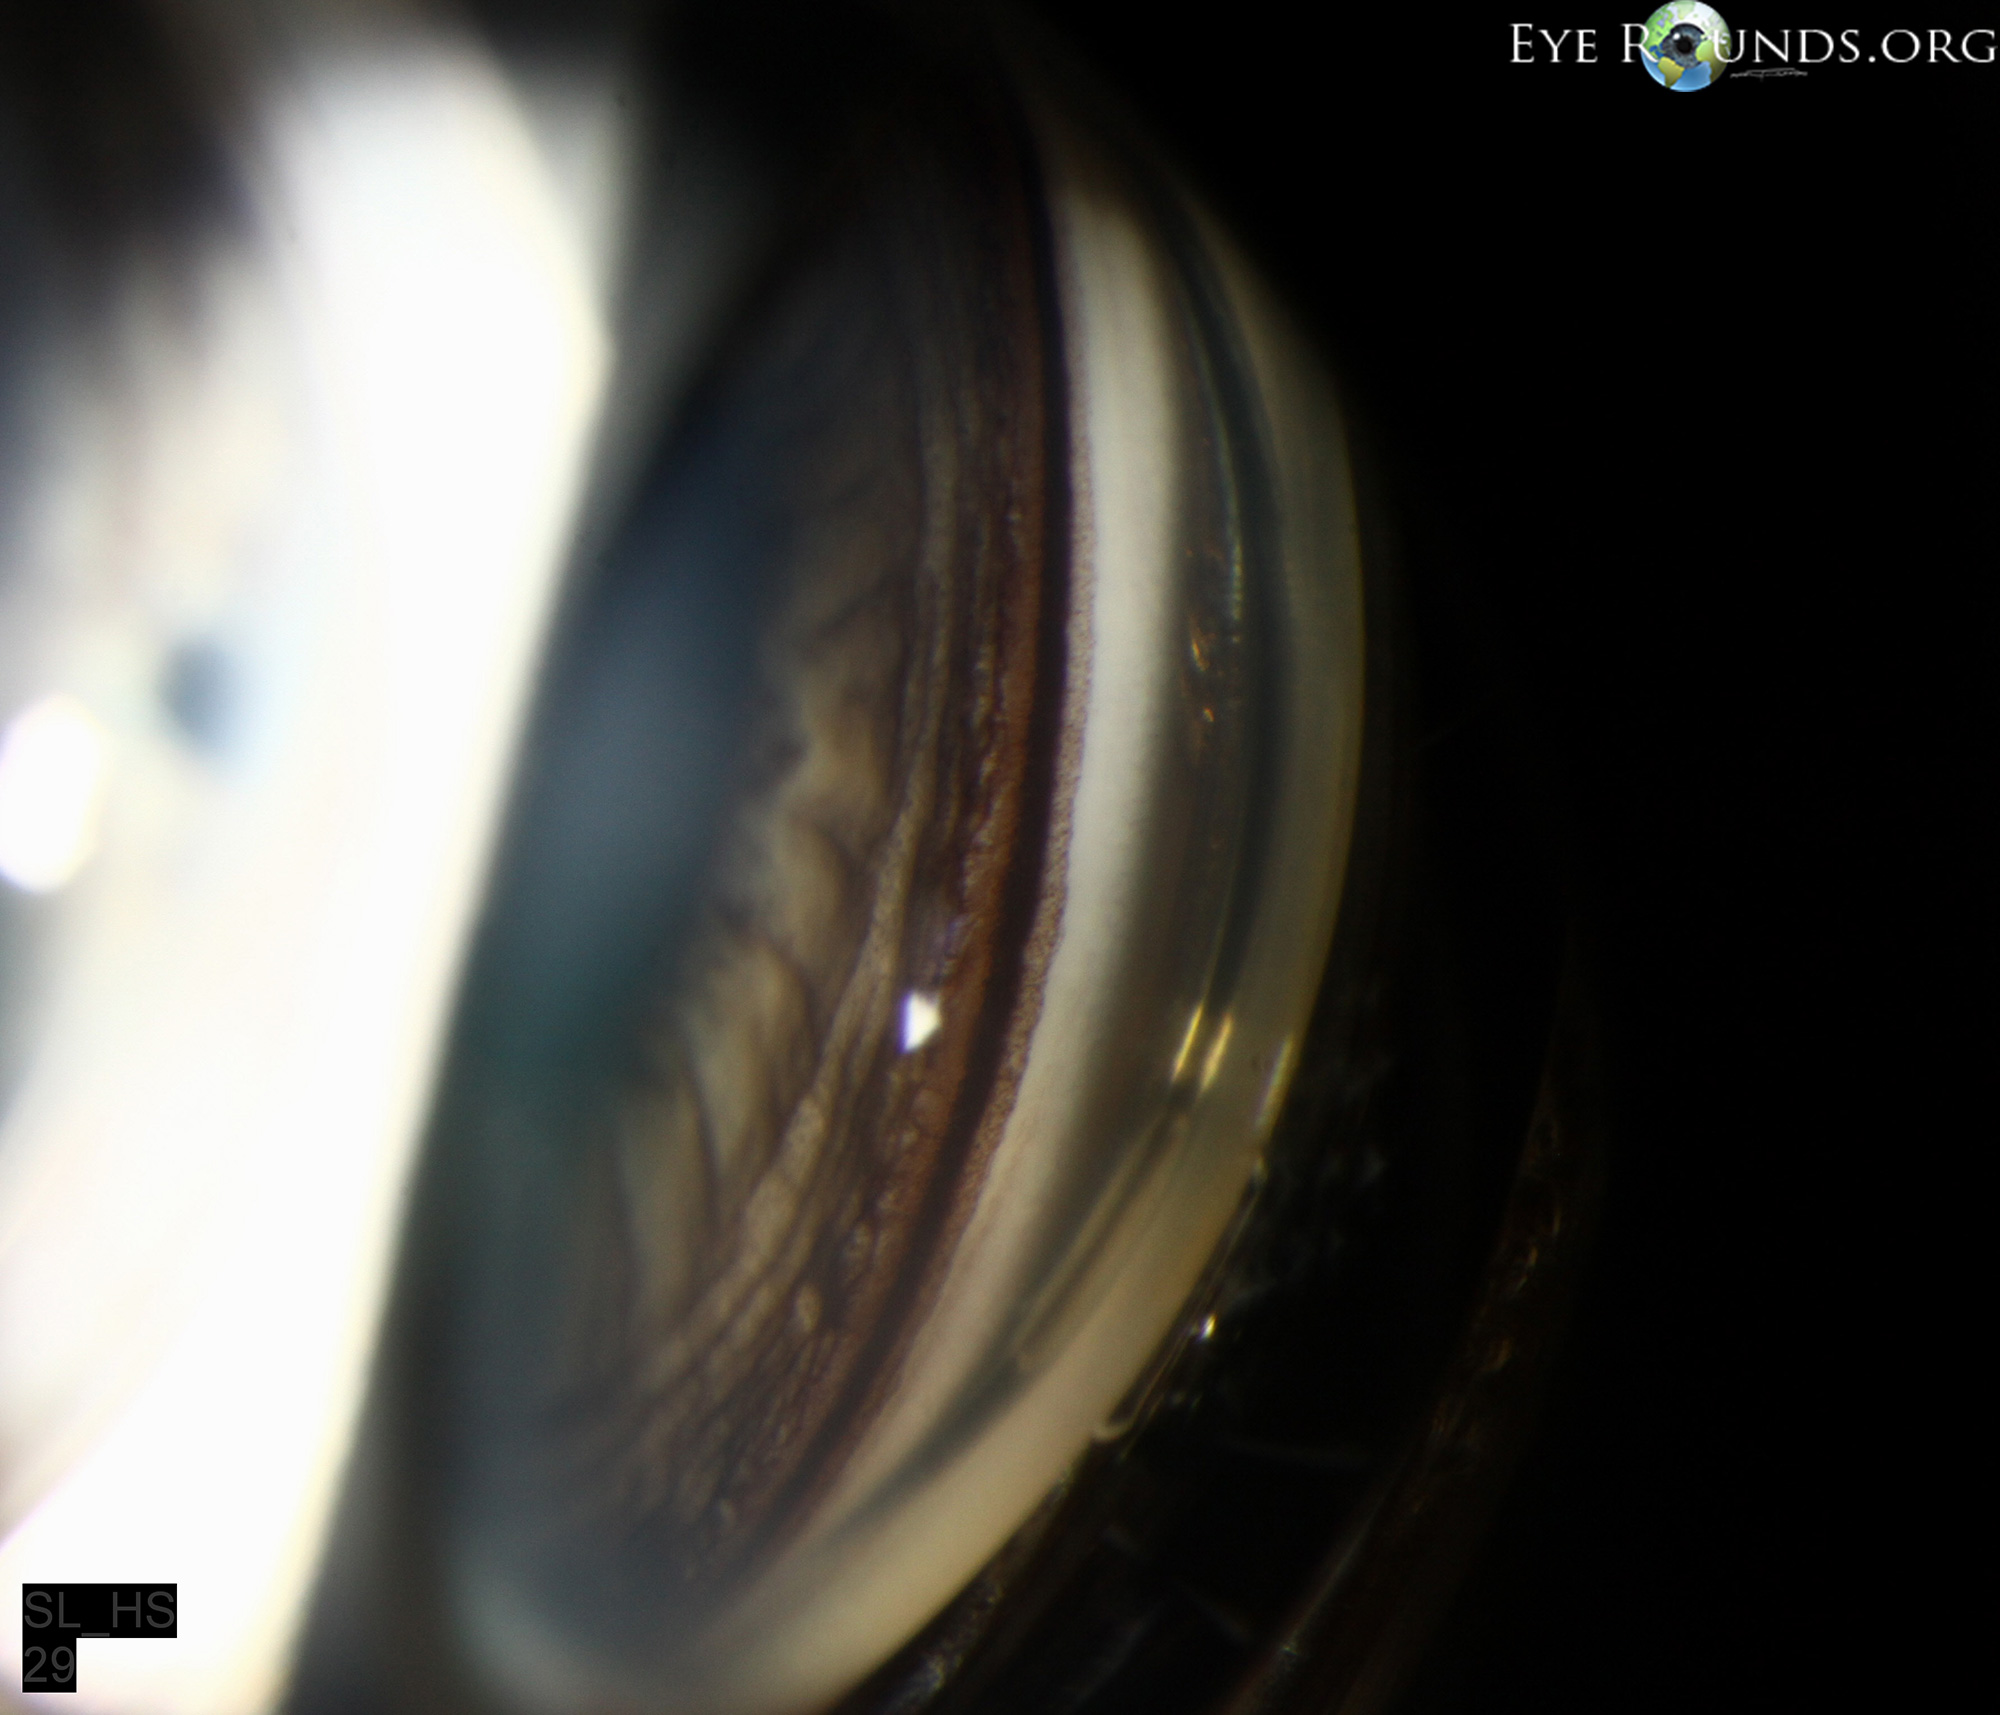

From www.eyerounds.org

Pigmentary Krukenberg's Spindle Krukenberg spindles are classically associated with primary pigment dispersion syndrome. Krukenberg spindles are an acquired form of retrocorneal pigmentation associated with intraocular pigment dispersion. Often the first sign of pds, a krukenberg spindle represents the vertical collection of pigment granules along the. Krukenberg spindle (kumar and acharya 2007). There are multiple exam findings that would indicate the presence of the. Krukenberg's Spindle.

Pigmentary Krukenberg's Spindle Krukenberg spindles are an acquired form of retrocorneal pigmentation associated with intraocular pigment dispersion. Krukenberg spindle (kumar and acharya 2007). There are multiple exam findings that would indicate the presence of the condition including a krukenberg’s spindle, sampolesi’s. Often the first sign of pds, a krukenberg spindle represents the vertical collection of pigment granules along the. Krukenberg spindles are classically. Krukenberg's Spindle.